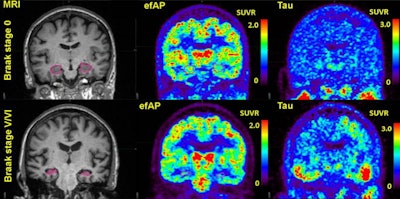

Comparisons of representative subjects. The first column highlights the hippocampus in pink on volumetric MRI. The second column shows early-frame amyloid PET (efAP) values from dynamic florbetapir-PET. The third column shows standard tau PET. Intensity scales for the PET images are shown as standardized uptake value ratios (SUVRs). Image courtesy of the Journal of Nuclear Medicine.In this study, the researchers hypothesized that early-frame amyloid PET could detect pathologic tau measurements in amyloid-positive patients on both dynamic amyloid and tau PET scans performed within six months of each other.

They analyzed scans of 63 patients who were amyloid-positive and 57 who were amyloid-negative. The ability of early-frame amyloid PET to stratify positive tau findings was measured using receiver operating characteristics analysis of the area under the curve (AUC). Patients were categorized as amyloid- and tau-positive or negative based on established cutoffs and were predominantly cognitively intact in both groups.

The researchers found that measurements with early frame amyloid PET within the hippocampus within the first three minutes of brain activity postinjection showed the strongest discriminative ability to stratify for tau positivity (AUC, 0.67-0.89 across tau PET regions) in amyloid-positive individuals. In addition, hippocampal early-frame amyloid PET correlated significantly with global tau-PET tauopathy scores in amyloid-positive patients.